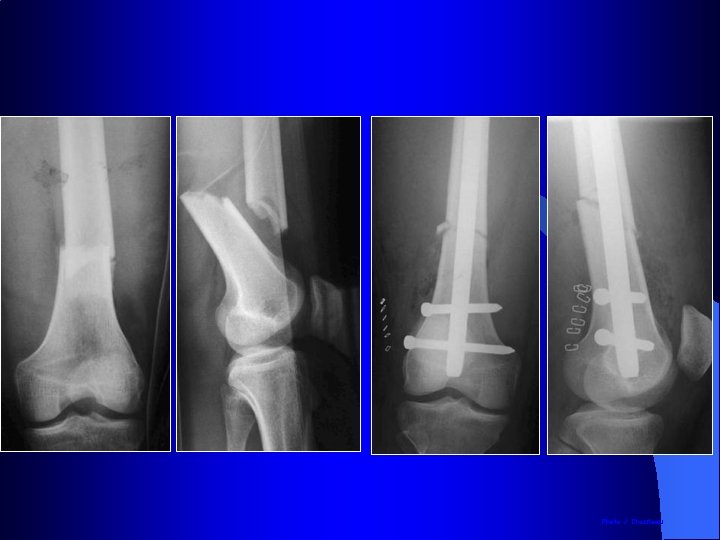

Indication des plaques : les fractures métaphysaires

Indication des plaques : les fractures métaphysaires Manuel AO